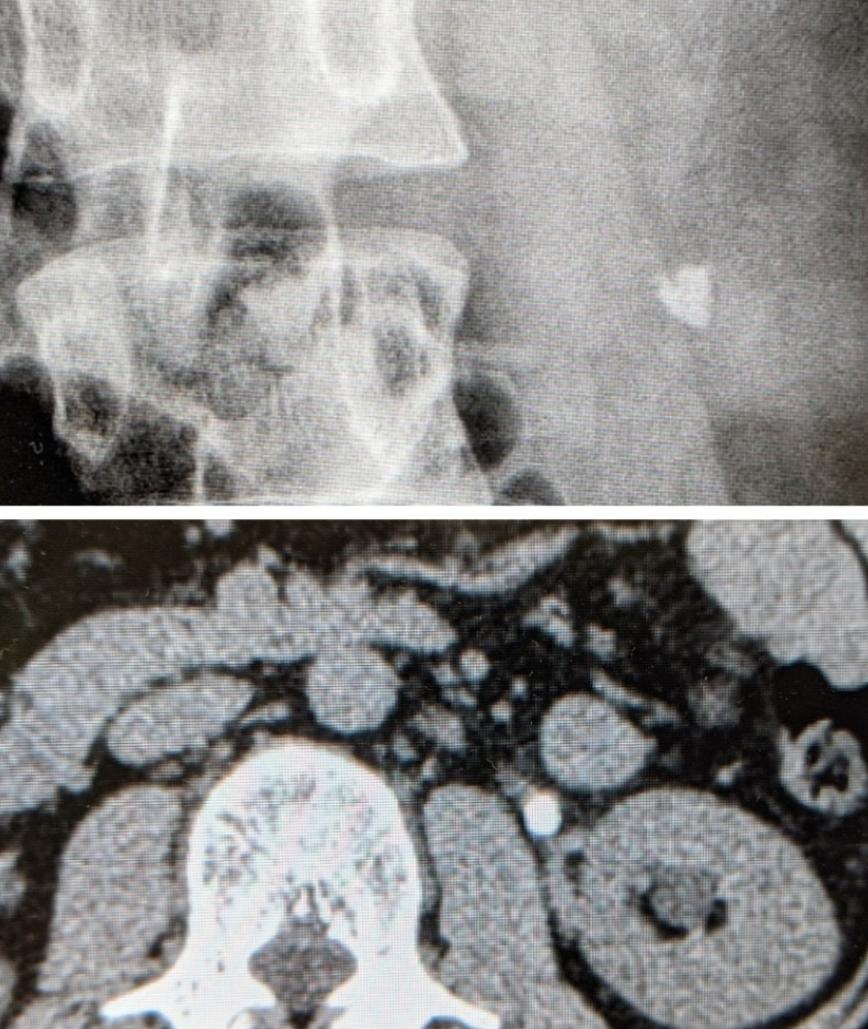

23: 風吹けば名無し 2022/04/29(金) 07:51:56.97 ID:5VUB2+/10

>>20

ワイ当時レントゲン撮ったけど、腎臓と陰茎の間の管(尿道)に出来てた。